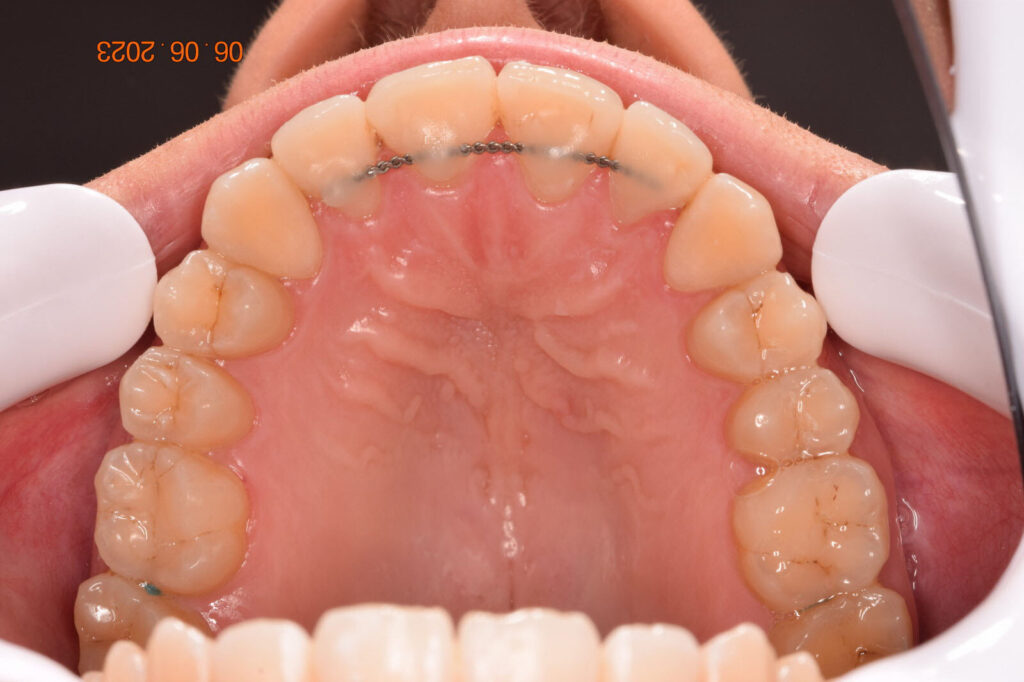

A 27-year-old female patient presented with class III malocclusion, 15 mm crowding in the upper arch, an anterior open bite, a lateral crossbite, and a total ABO score of 29. Her facial profile was straight with a retrusive maxilla, and the upper and lower incisors were retroclined. An extreme lack of midface support was also noted, and the constricted dental arches resulted in a poor smile width and dark buccal corridors. No myofunctional investigations were performed at the time, as they were initially considered unnecessary.

Adhering to the principles of Face First Orthodontics, the primary objective was to increase midface support by expanding the upper maxilla, fixing the cross bite, and aligning the teeth. Closing the open bite was a secondary objective.

The treatment began in 2017. Given the patient’s preference for less visible brackets, Damon Clear brackets were selected. High torque upper cuspids and low torque upper incisors were chosen to offer the best torque control for upper arch development. For the lower arch, there were no alternative bracket configurations available. Bite turbos were applied to the upper second molars.

The teeth are in a very good position and the bone has reshaped.